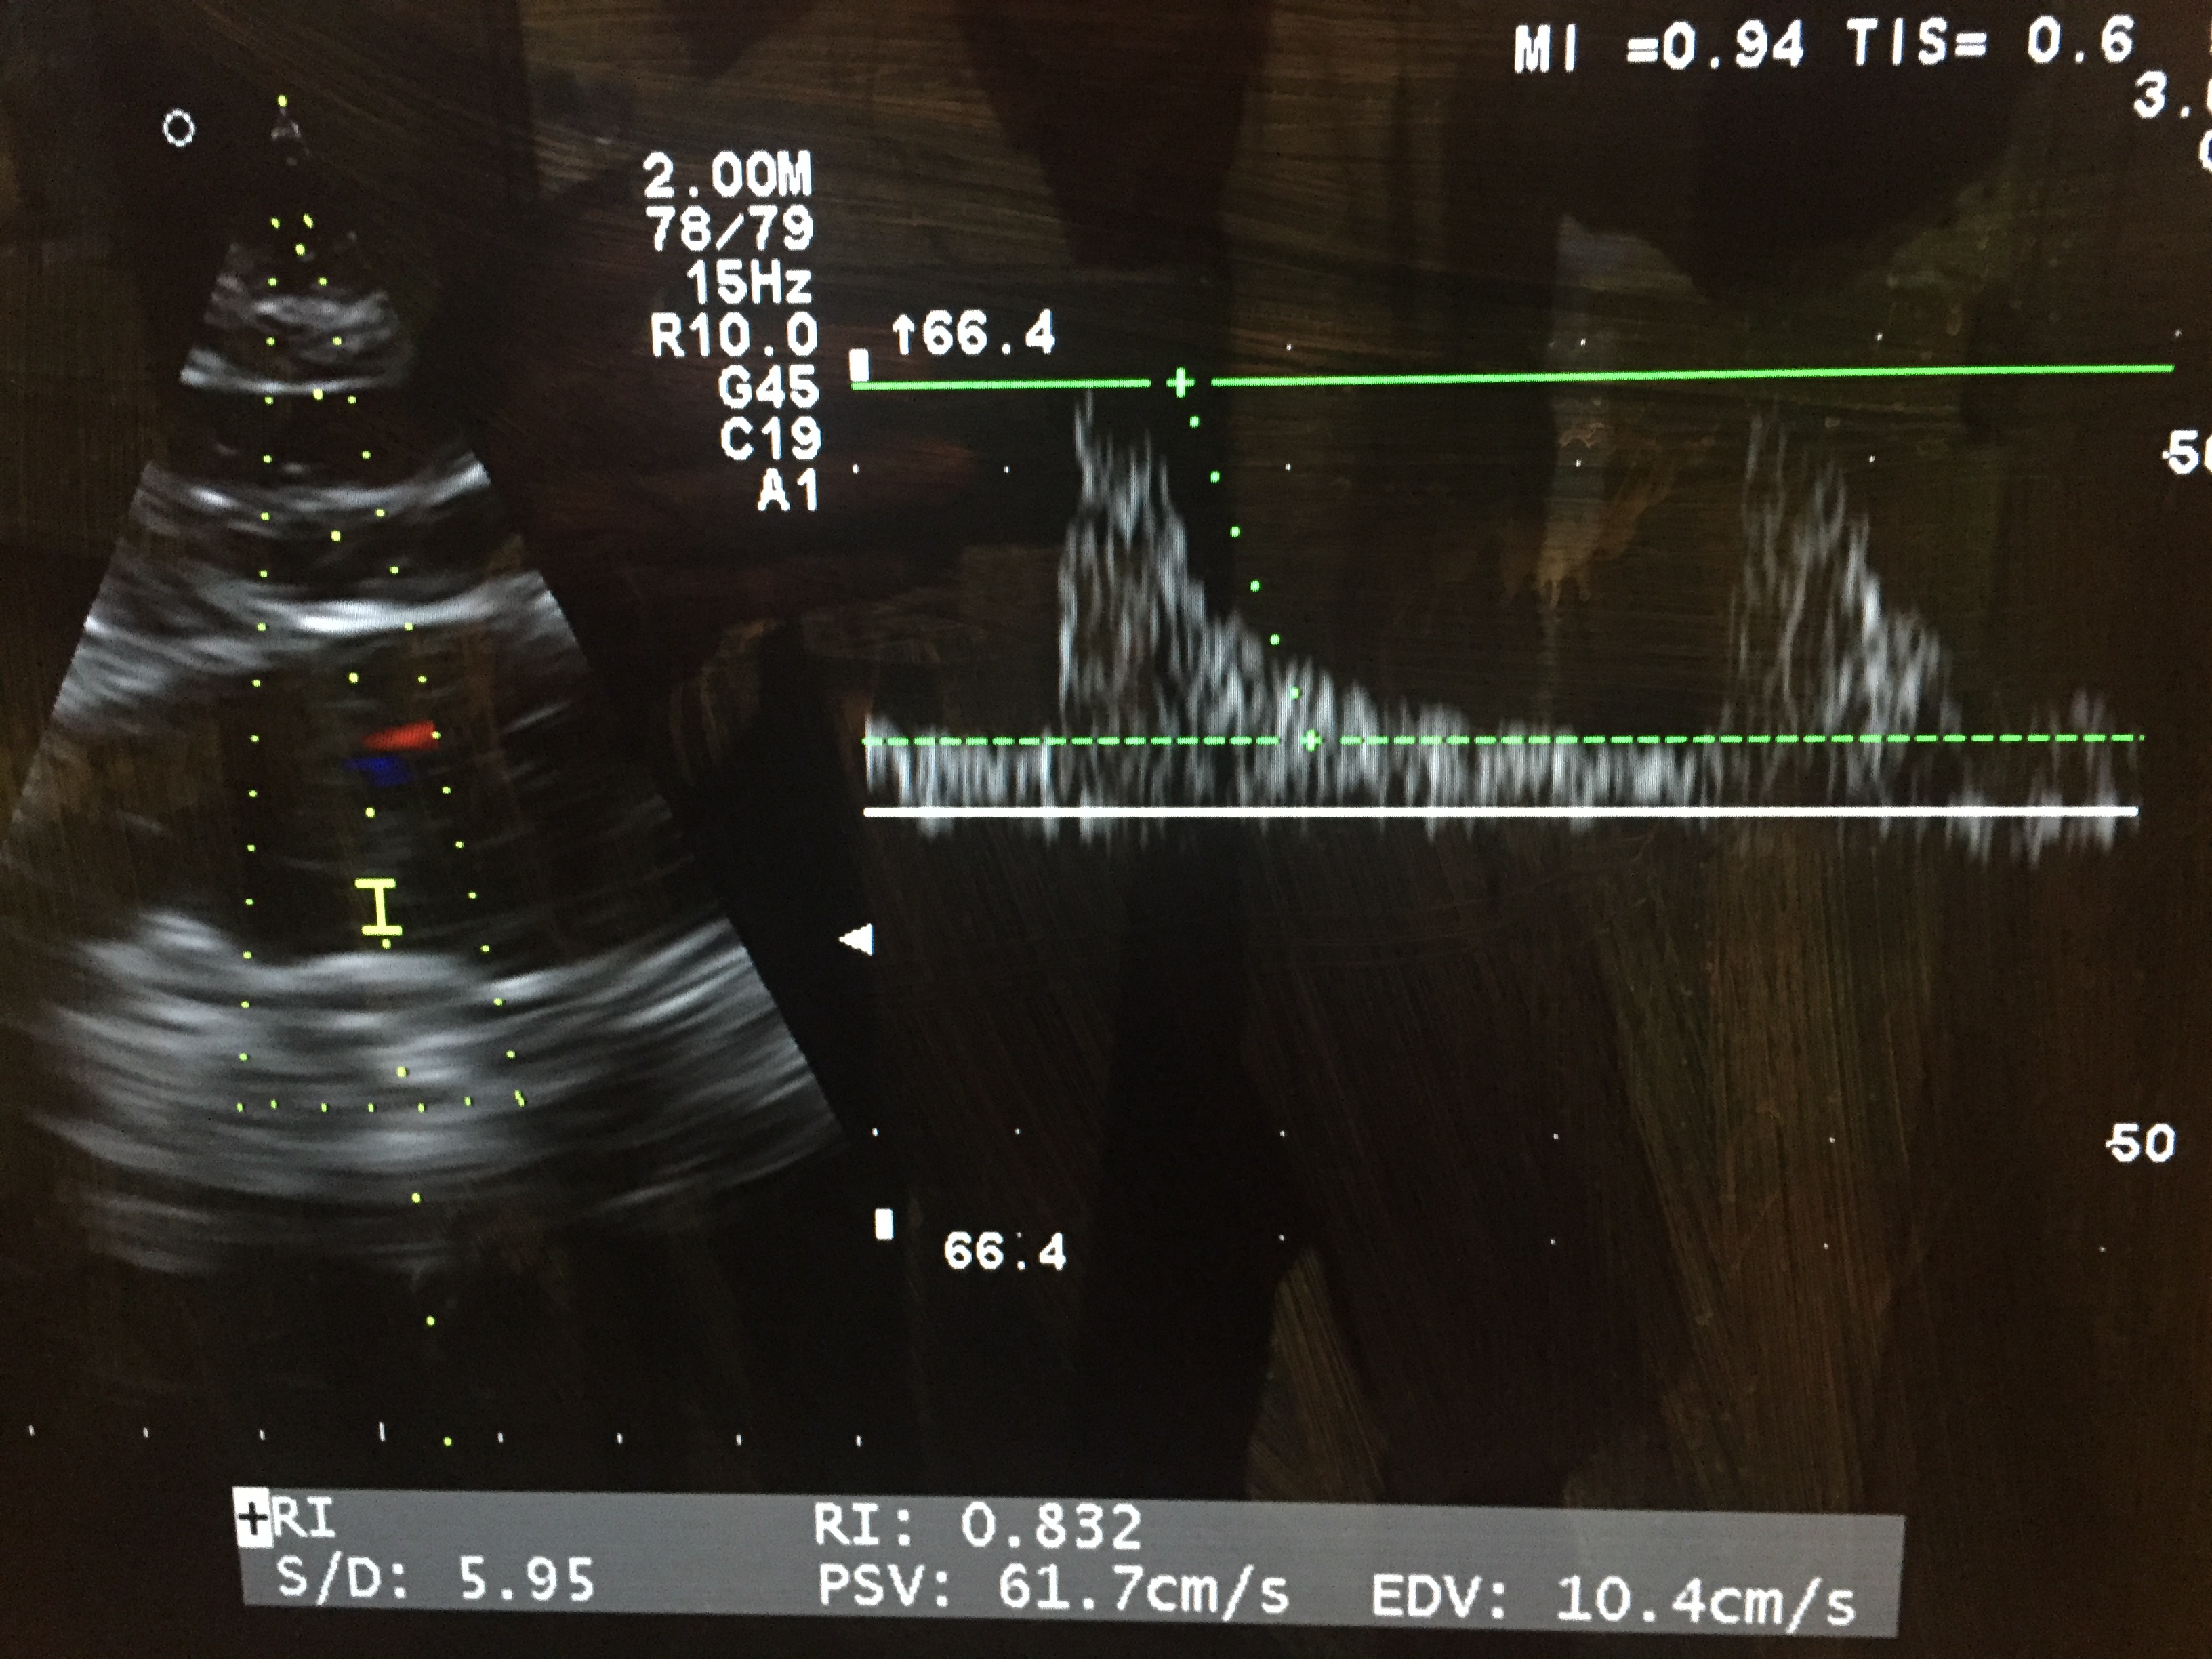

The NE gtt increased his MAP to 75 mmHg. His SV was 80, CO 7.1 (I was a little surprised it didn’t go down a bit), estimated SVR was 700. I had his labs back at this point and his creatinine was 1.8 and the last creatinine we had was 1.1 a few months ago. His renal vein pattern was still biphasic and his renal resistive index was also still quite high at 0.89, which would probably predict a significant kidney injury in 2-3 days.

Even though his MAP and hemodynamics looked great, I was worried about the renal resistive index. I ordered a little more furosemide and started him on a little bit of a vasopressin infusion. After things settled down, MAP was 75-80, his average SV was 80, CO 7.3, estimated SVR was about 800, and his renal resistive index (RRI) was 0.75. He looked much better too. The second lactate was 1.3.